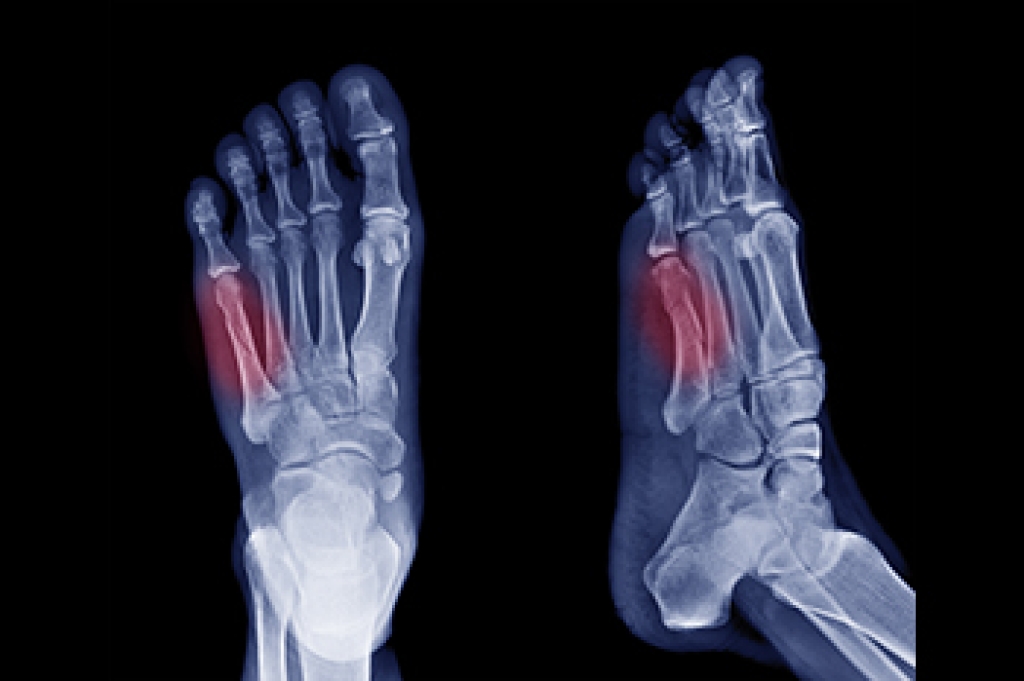

Diabetic limb salvage is the attempt of saving a limb, such as the foot, that has an infected ulcer, from amputation. Podiatrists also try to make sure that there is enough function in the foot after the salvage that it is still usable. Those with diabetes experience poor blood circulation, which prevents proper healing of an ulcer. If the ulcer is left uncheck, it could become infected, which could result in the need for amputation.

Limb salvage teams have grown in recent years that utilize a number of different treatments to save the infected limb. This includes podiatrists that specialize in wound care, rehabilitation, orthotics, and surgery. Through a combination of these methods, limb salvage has been found to be an effective treatment for infected limbs, and as an alternative to amputation. Podiatrists will first evaluate the potential for limb salvage and determine if the limb can be saved or must be amputated.